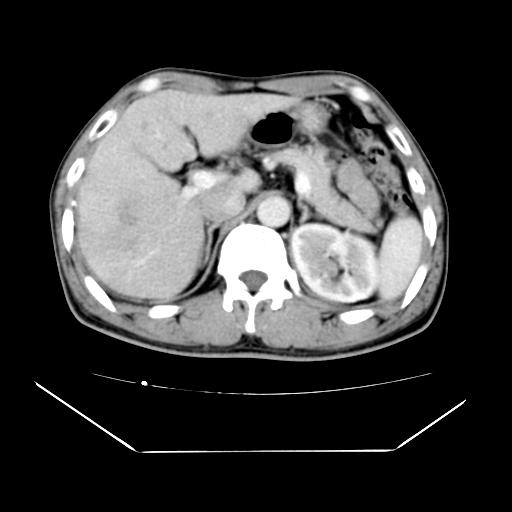

男性,55岁,外院体检afp明显升高,但b超未发现异常,否认乙肝病史。来我院ct增强。有延时扫描。

延时扫描完全充填,血管瘤

肝脏右叶动脉期可见低密度影,至延迟期被充填,考虑血管瘤可能性大。

肝右叶病灶

不排除肝右叶肝癌可能。

肝6段血管瘤

血管瘤可能性大。

考虑肝右静脉影。